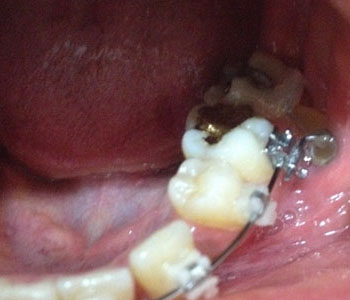

이번 월치료때 가장 큰 핵심적 치료가 바로~~ 오른쪽 하악 어금니에 와이어를 연결했어요.!

누워있는 어금니를 반듯하게 세우기 위해서 와이어를 연결하여 주었는데요~

교합이랑 치아 상태를 고려해서 원장님께서 손수 와이어 세팅하시고~

치위생사 선생님께서 부착하셨는데.. 첫번째 두번째 실패하고... 세번째 시도만에 드디어 부착.!

부착이 안되면 어떡하나 했는데.. 다행이 잘 부착되었답니다.^^

와이어가 잇몸 가까이 닿아있다보니 잇몸 다칠까봐

몇번이고 물어봐주시면 꼼꼼하게 실리콘 부착까지 해주셨어요.